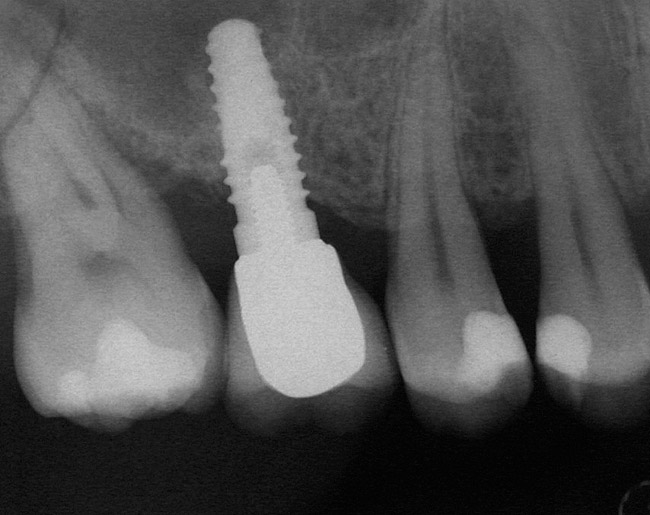

A 45-year-old female was referred for implant placement and prosthetic treatment in the area of tooth No. 24. The tooth had been extracted 4 years prior; the patient did not wear any denture thereafter. The radiograph revealed adequate bone height and a 5-mm to 6-mm ridge at the crest (Figure 2). It was decided to place a 11.5 mm in length, 3.75 mm in diameter Tapered Screw-Vent® implant (Zimmer Dental, www.zimmerdental.com) using the alveolar remodeling technique in the area of tooth No. 24.

Figure 2 Preoperative view of the area around tooth No. 24. On the left, a previously placed implant abutment

is visible.

Figure 4  Implant positioning; the radiograph taken 4 weeks after placement confirmed good primary stability.

Figure 2  Preoperative view of the area around tooth No. 24. On the left, a previously placed implant abutment is visible.

Figure 2

Figure 4